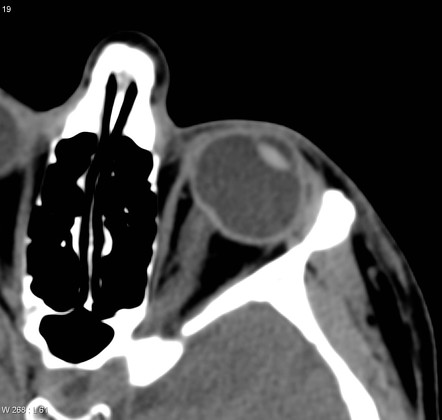

혈액공급을 마치고 난뒤의 정맥의 경우,

시신경유두는 망막중심정맥(central retinal vein)을 통해서 모이고

시신경 유두주위에서는 Vortex vein 을 통해서 모인다고알려져 있습니다.